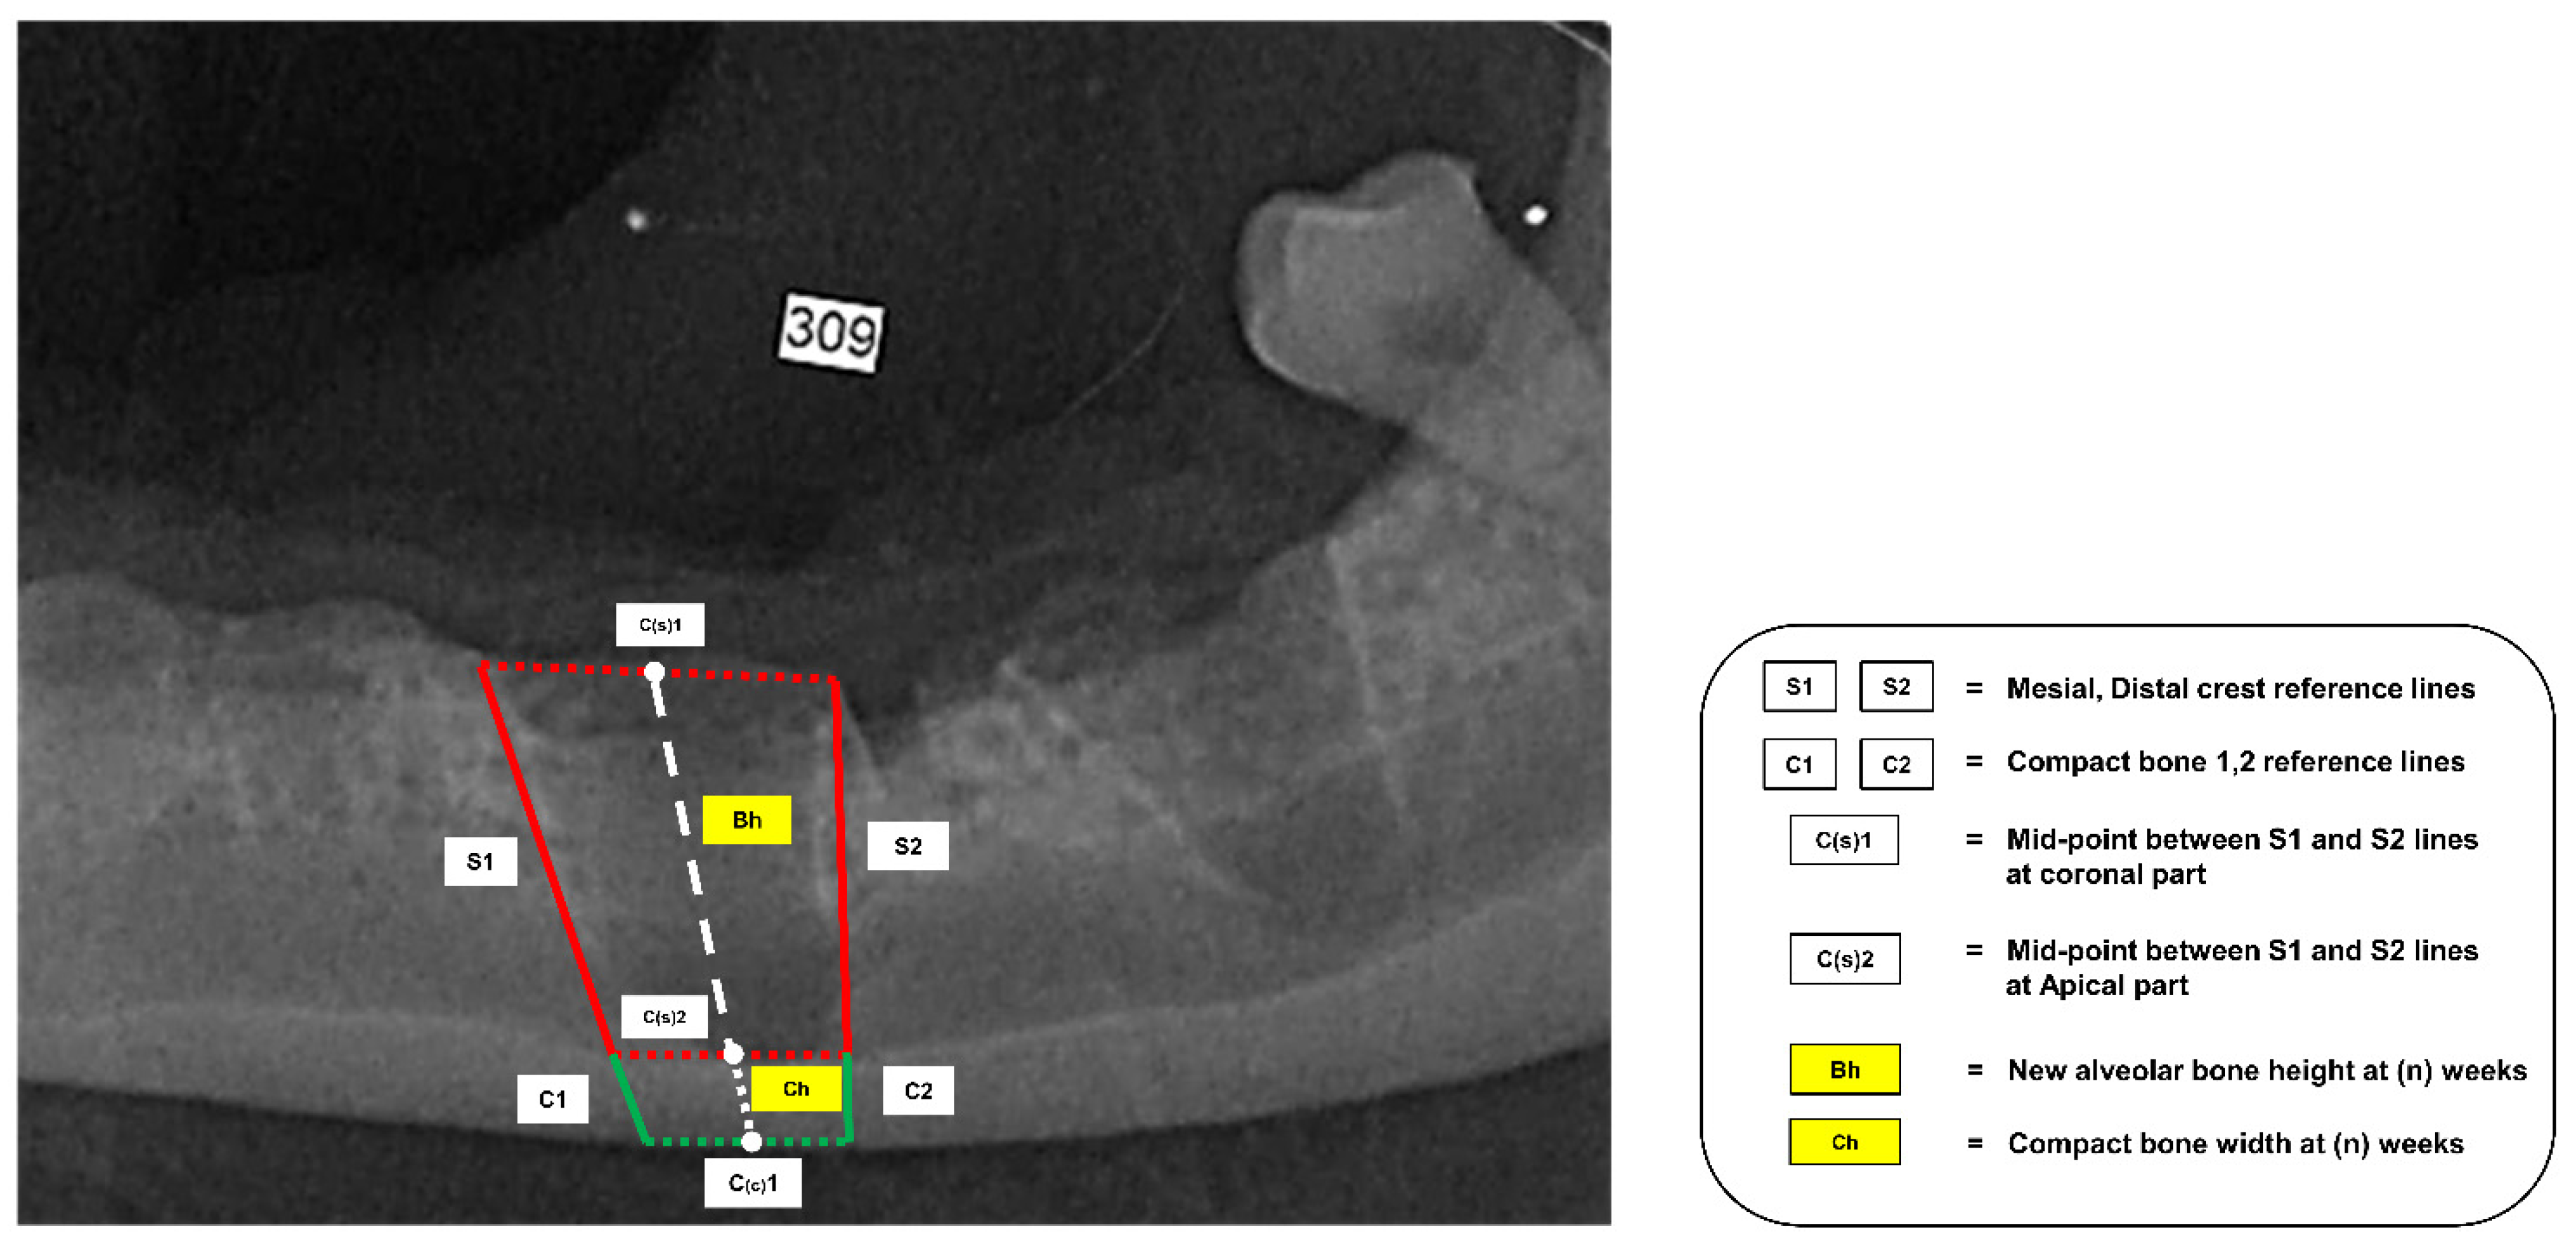

2.7. New Alveolar Bone Height Measurement

2.8. Alveolar Bone Density Analysis